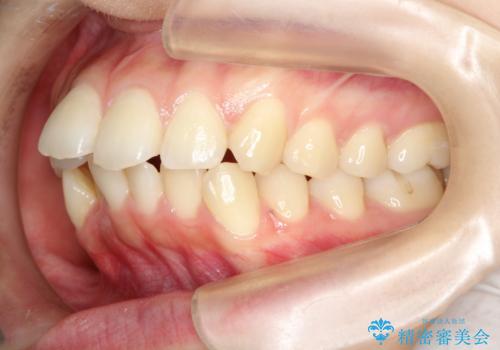

目立たない裏側装置 ハーフリンガルの抜歯矯正

- 口元の突出感を気にして来院された患者様です。

上下左右の第一小臼歯4本を抜歯して口元を下げる治療計画としました。

目立たない装置が希望であったため、上顎が裏側装置である、ハーフリンガル装置を選択されました。